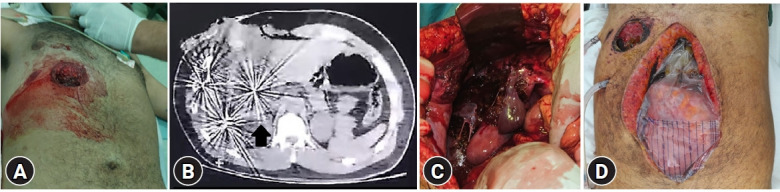

This report presents the case of a 20-year-old man who sustained a severe liver injury from a close-range shotgun blast. A prompt medical intervention, including damage control exploratory laparotomy and surgical debridement, was undertaken due to the extent of liver damage. Despite challenges such as a nondirected biliary fistula and extensive liver parenchymal injury, comprehensive surgical management led to successful treatment. Postoperative complications, including biloma and fungal infection, were managed appropriately, highlighting the importance of vigilant follow-up care. The case underscores the complexity of managing severe liver trauma and emphasizes the evolving role of trauma damage control strategies and minimally invasive procedures in achieving favorable outcomes.